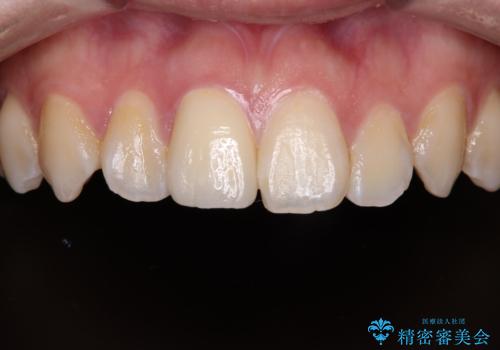

土台の形を整えて、精度の高いシリコーンによる型どりを行いました。

セラミックが入るまでの間は仮歯にしています。

樹脂の材料では再現できない自然な前歯に仕上がりました。